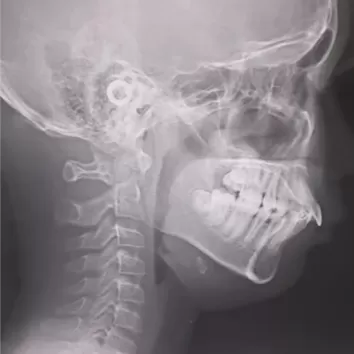

Rayons X avant le traitement

[Radiographie panoramique/Céphalogramme latéral]